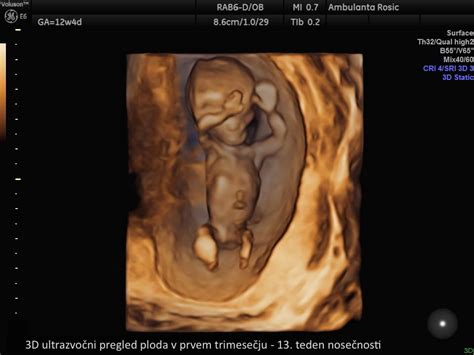

Prvo trimesečje obsega obdobje od 1. do konca 13. tedna nosečnosti. To je začetna in pogosto najbolj intenzivna faza, ki se začne s trenutkom spočetja. V tem obdobju se iz ene same oplojene celice (zigote) razvije zarodek, ki se ugnezdi v steno maternice. Kljub majhni velikosti, ki je primerljiva z velikostjo breskve, se v tem času položijo temelji za vse ključne organe in telesne sisteme otroka.

- 9. do 13. teden: Skladno z razvojem potez obraza, žrela, brade in ust, otrok postaja bolj prepoznaven. Vidijo se roke, prsti, dlani in stopala, sposobnost odpiranja in zapiranja pesti postaja vidna. V tem obdobju plod doseže približno 6 cm in tehta okoli 14 gramov.